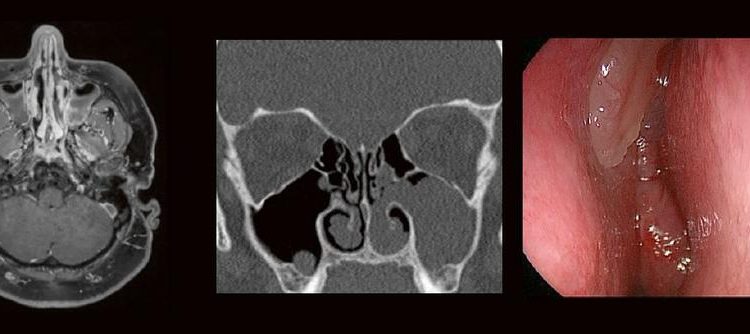

Dr. med. André ReisbergDr. med Sebastian Plößl Die bildgebende HNO-Diagnostik macht es Anfängern nicht leicht. Die Anatomie ist komplex und weniger intuitiv als in anderen Körperregionen. Normvarianten erschweren insbesondere in den Nasennebenhöhlen den Lernprozess. Sobald pathophysiologische Zusammenhänge verstanden und wichtige klinische Aspekte verinnerlicht wurden, gelingt es einen praxistauglichen, belastbaren Befund zu erstellen. Wo muss ich […]